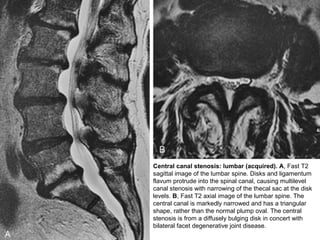

Central canal stenosis: lumbar (acquired). A, Fast T2

sagittal image of the lumbar spine. Disks and ligamentum

flavum protrude into the spinal canal, causing multilevel

canal stenosis with narrowing of the thecal sac at the disk

levels. B, Fast T2 axial image of the lumbar spine. The

central canal is markedly narrowed and has a triangular

shape, rather than the normal plump oval. The central

stenosis is from a diffusely bulging disk in concert with

bilateral facet degenerative joint disease.